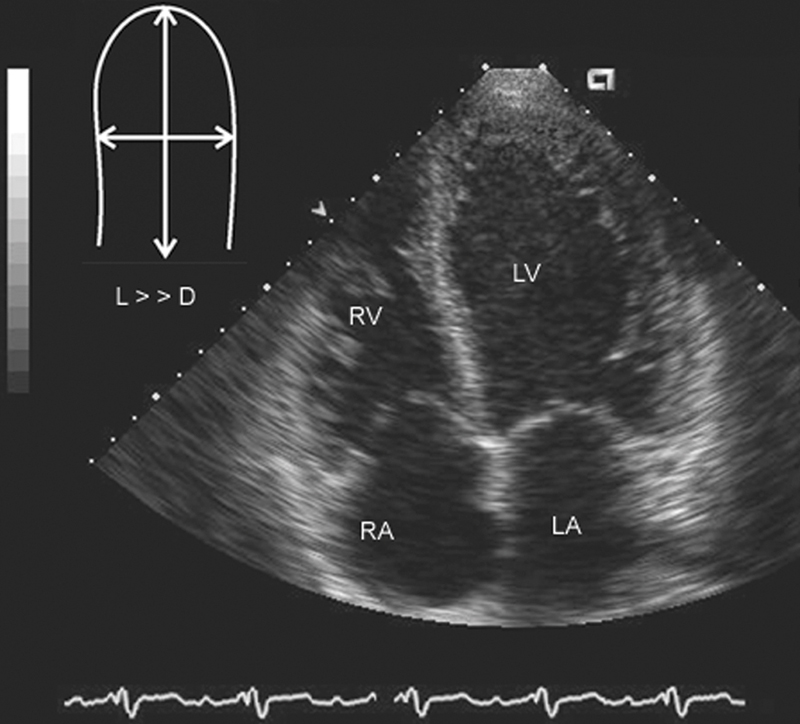

فحوصات تشخيصية لبعض امراض القلب والشرايين التاجية